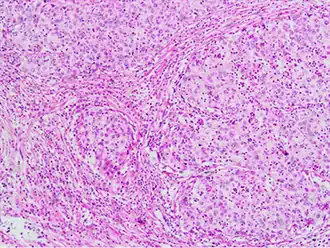

This large squamous carcinoma (bottom of the picture) has obliterated the cervix and invaded the lower uterine segment. The uterus also has a round leiomyoma up higher.

Often, before the biopsy, the doctor asks for medical imaging to rule out other causes of a woman's symptoms. Imaging modalities such as ultrasound, CT scan, and MRI have been used to look for alternative disease, spread of the tumor, and effect on adjacent structures. Typically, they appear as heterogeneous masses on the cervix.[64]